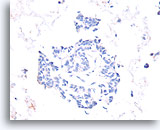

Lobulair carcinoom, Borst FNA, celblok.

Lobulaire carcinoomcellen lijken in het stromaweefsel te zijn ingebed, zodat de indruk wordt gewekt van hypercellulariteit. Dit kan de reden zijn waarom cytologische preparaten van een lobulair carcinoom vaak weinig maligne cellen tonen.

20X

Lobulair carcinoom, Borst FNA, celblok.

Lobulaire carcinoomcellen lijken in het stromaweefsel te zijn ingebed, zodat de indruk wordt gewekt van hypercellulariteit. Dit kan de reden zijn waarom cytologische preparaten van een lobulair carcinoom vaak weinig maligne cellen tonen.

20X